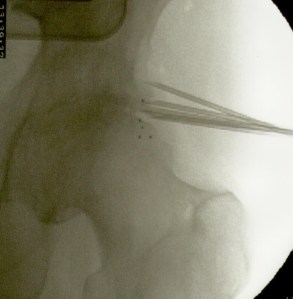

La artroplastia total de cadera para los casos de coxartrosis severa es el tratamiento de elección de la gran mayoría de cirujanos ortopédicos. Sin embargo cuando el paciente es menor de 50 años suele diferirse la intervención debido al tiempo de sobrevida del material protésico. También lo es en pacientes con deterioro del estado general debido a la avanzada edad o a enfermedades concomitantes (cardiópatas, por ej.) En estos casos la colocación de microimplantes de oro periarticulares alrededor del cuadrante súpero externo de la articulación es, habida cuenta del resultado sintomático y funcional, el tratamiento más indicado. La fácil colocación mediante control radioscópico y la rapidez de la recuperación (inmediata) hacen que este procedimiento sea seguro y muy útil para la remisión del dolor y la rigidez. No necesita ingreso ya que es una cirugía ambulatoria, se efectúa con anestesia local, y el paciente sólo requiere reposo relativo en el día de la intervención. Los resultados mediatos son excelentes. La mejoría clínica aumenta con los meses debido a la difusión de las nanopartículas de oro, por lo que contrariamente a los tratamientos convencionales que disminuyen su efecto con el tiempo, los microimplantes de oro lo mejoran. En cuanto esta técnica se popularice se reducirá significativamente el número de artroplastias.

Más abajo se observarán unas imágenes de casos de implantes de oro en cadera